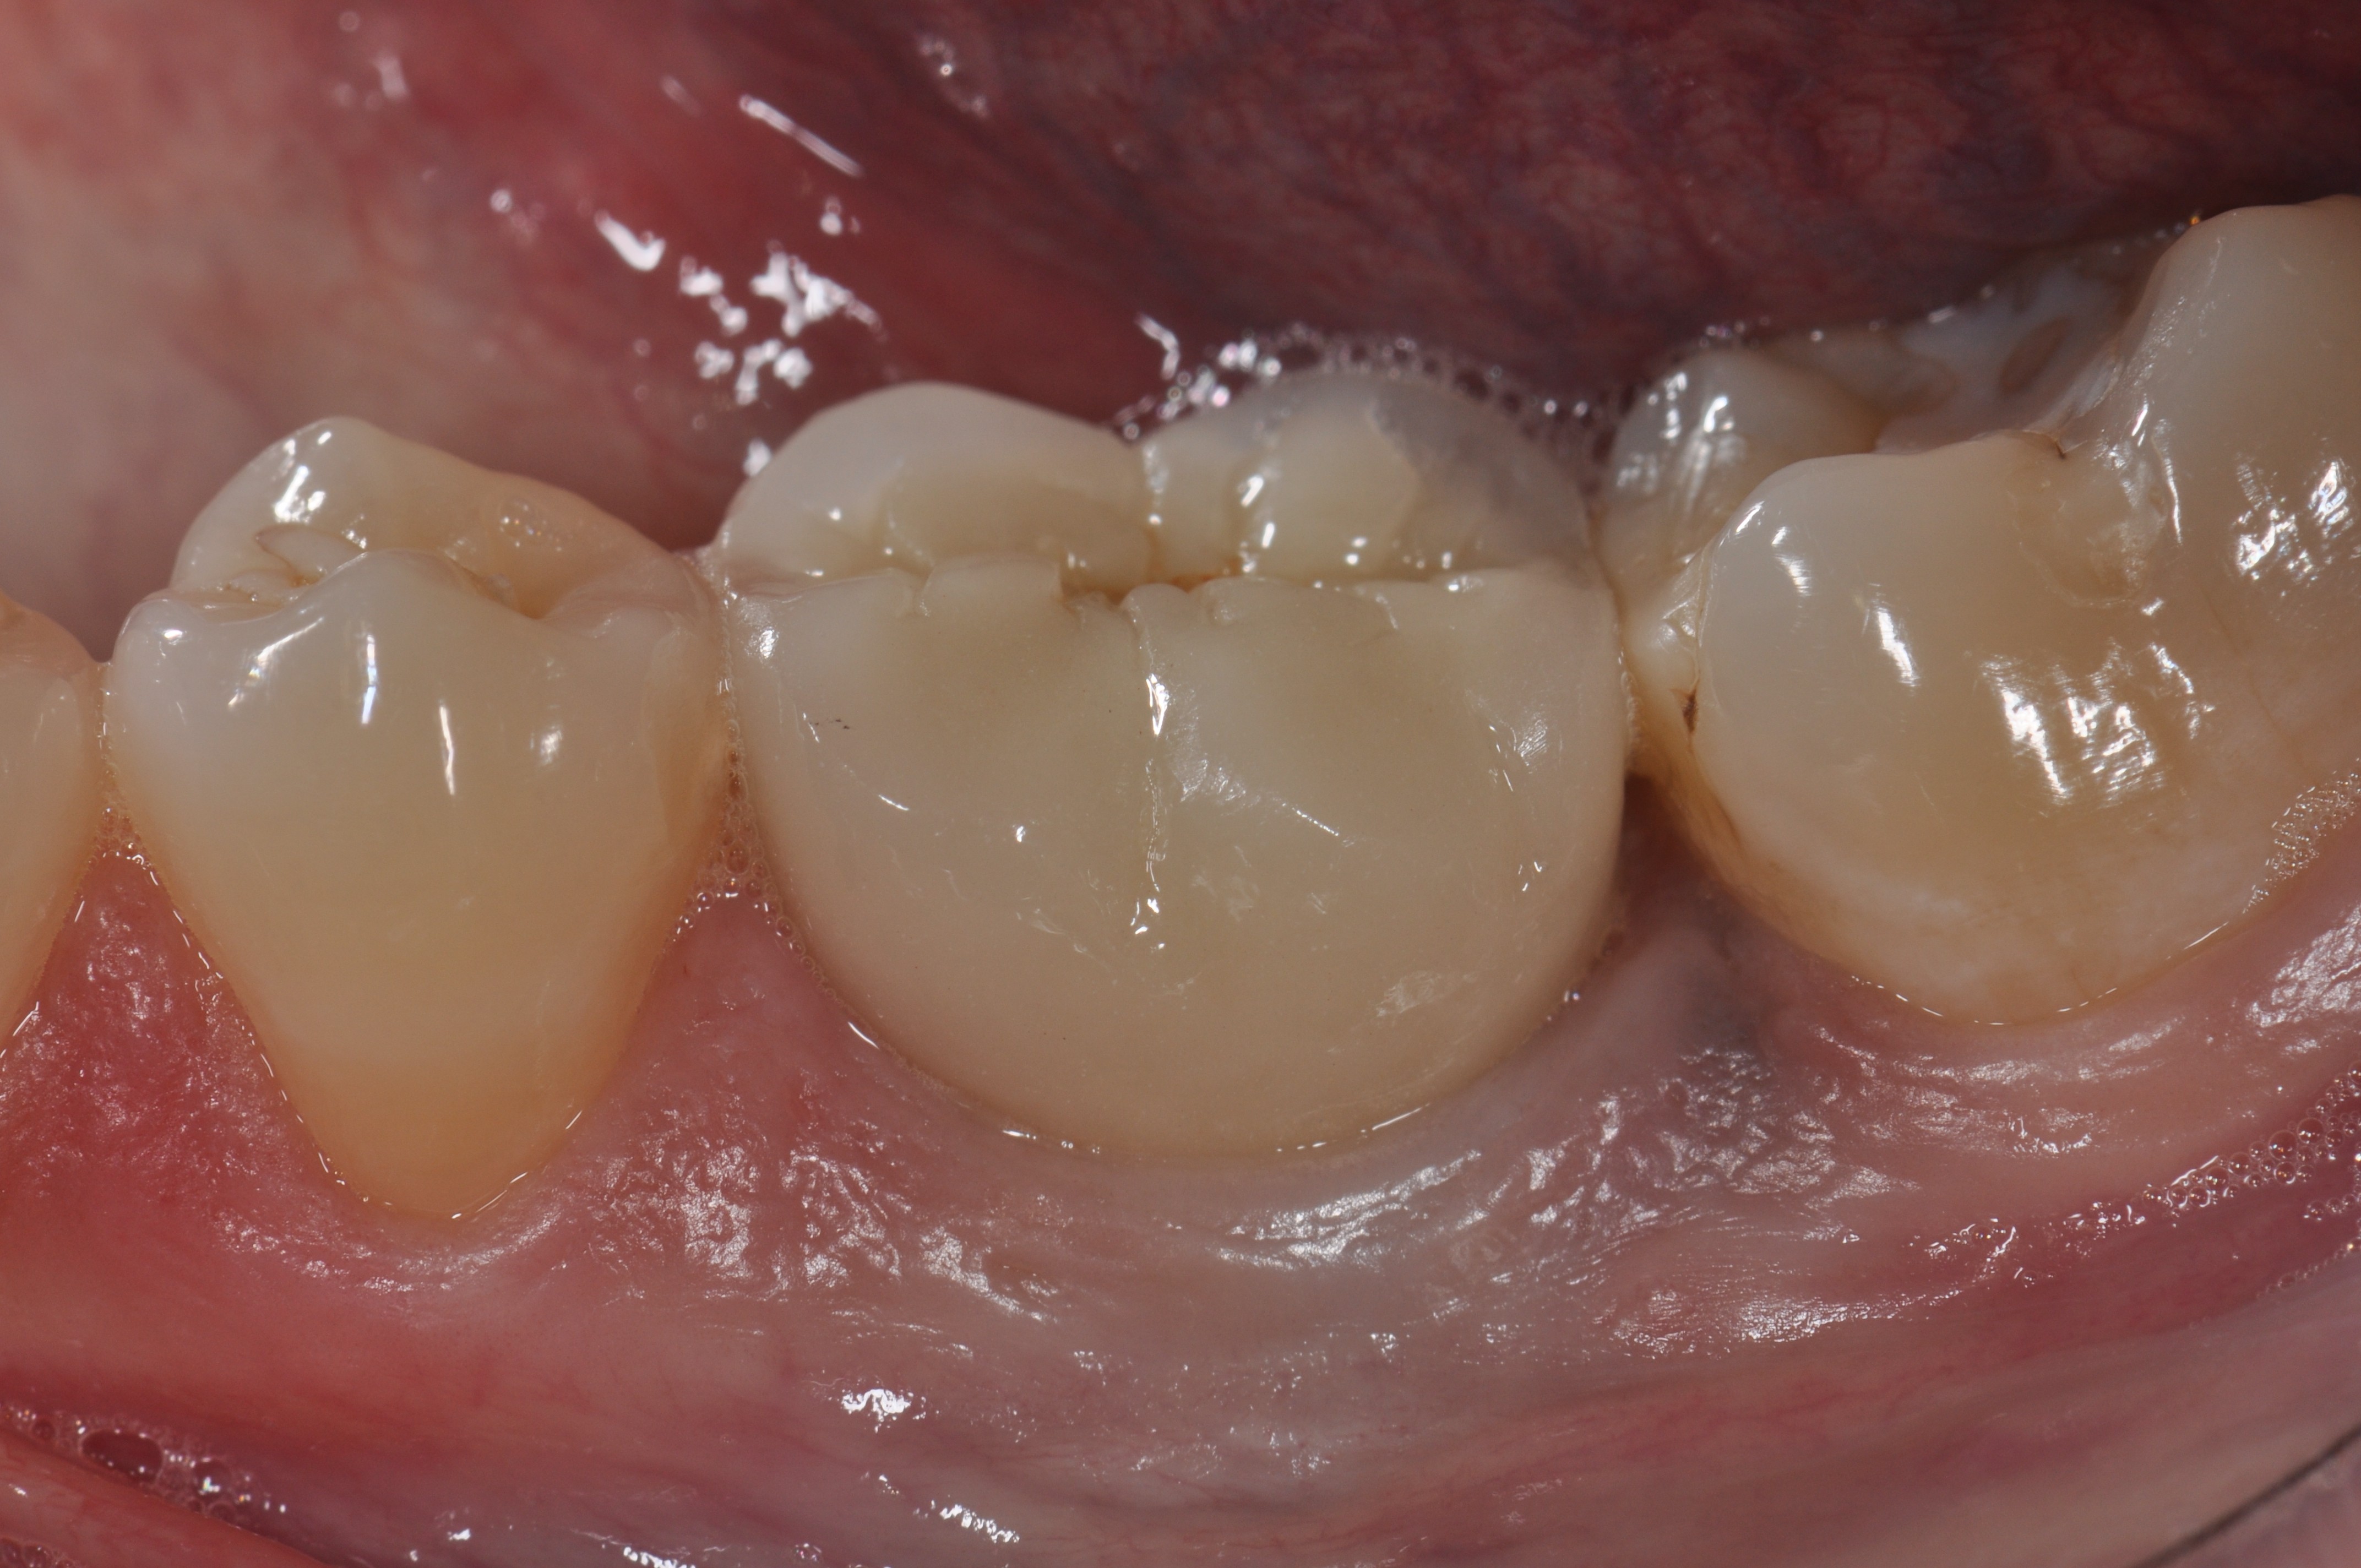

Fig 6. A clinical view of this area suggests that peri-implant mucositis is present. The tissue is swollen, it bleeds on probing, has 5 mm of probing depth, and exhibits purulent exudate.

Figure 6